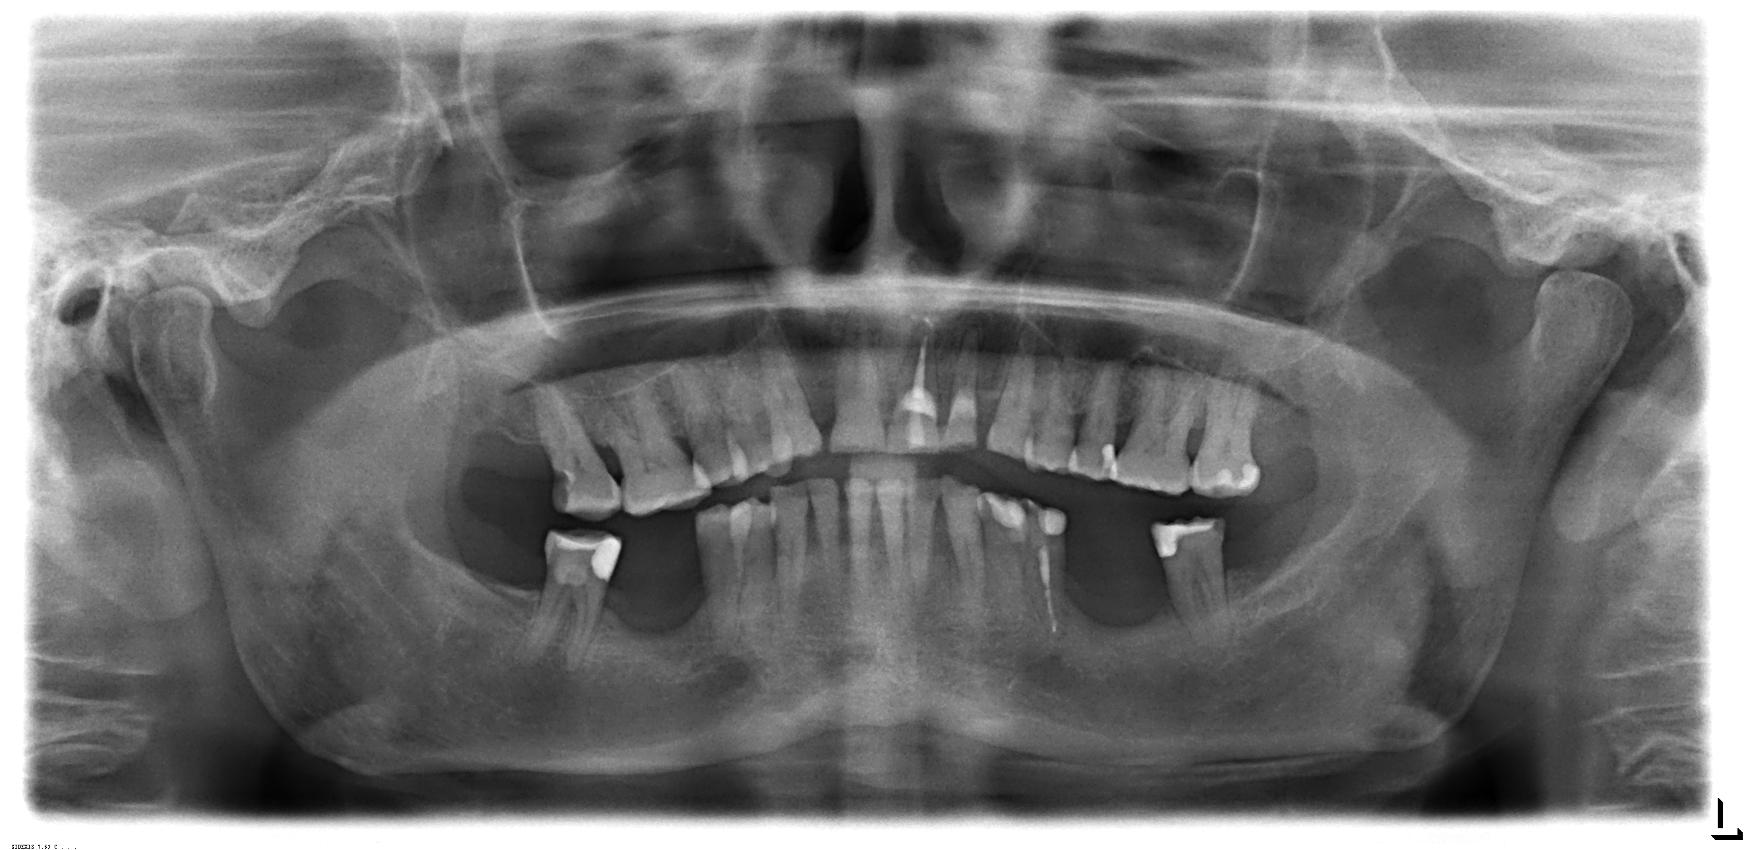

2 Implantate setzen mit Kronen

I. Befund des gesamten Gebisses / Behandlungsplan

Oberkiefer

Unterkiefer